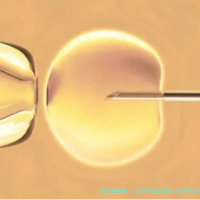

目前主流的试管婴儿技术分为三种:一代技术主要解决女性输卵管问题,让精卵在体外自在结合;2代技术针对男性精子问题,通过单精子注射方式强行做到受精;三代技术则是在胚胎移植前进行遗传生物学筛查,有效预防遗传性疾病传递,实现优生优育。

取卵和取精通常在同日进行,取出的卵子和精子在实践室中进行受精和培养。胚胎培养三至五天后,医生懂得挑选择一至两个优质胚胎移植入子宫。移植后仍旧要黄体支持治疗,约14天后即可进行妊娠检查。